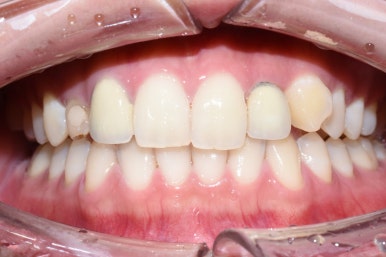

웃을 때는 이런 식으로 보이는데요,

인공물인게 티가 거의 나지 않으면서도 고르게 완성되었습니다.

제일 앞에서 많이 보이는 치아이다 보니

앞니 6개만 했지만 다른 치아들까지 환해 보이는 효과가 있습니다.